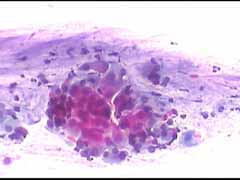

Στο ιατρείο μας διενεργούμε από ανέκαθεν την λήψη, χρωση κι άμεση μικροσκοπική εξεταση ενός επιχρίσματος κατά Papanicolaou. Για τον σκοπό αυτό εφαρμοζουμε την κλασική χρώση κατά Παπανικολάου και κατα τελευται 4 χρόνια επιπλέον και την χρώση Cytocolor της εταιρειας Merck , που διαρκεί μονον 4 λεπτά και δινει εντυπωσιακές εικόνες, ειδικά στην απεικόνιση των αδενικών κυττάρων. Τα παρακάτω περιστατικά είναι μία επίδειξη φυσιολογικών κυτταρολογικών εικόνων γυναικών στην εμμηνόπαυση και κλιμακτήριο..

Aσθενής: Tζιτ. Μ. Ετος γεν. 1943. Ετησιες προληπτικες εξετάσεις σε μας από το 1992. Εμμηνόπαυση απο το 1992 _Προληπτική εξέταση Οκτ. 2009

Papanicolaou. Πλακώδη επιθηλιακά κύτταρα της κυρώς της διαμέσου και λιγότερο της επιφ. στοιβάδας, με σποραδική οξεοφιλία .Αρκετά παραβασικά, καθώς και αρκετά κύτταρα ενδοτραχήλου κατά μόνας και καθ΄ ομάδας.. Λίγα πολυμορφοπύρηνα. Καθαρό υποστρωμα.. Μικρού βαθμου ατροφίας επιθηλίου. Αρνητικό για κακοήθεια..Φυσιολογικό για την ηλικία.